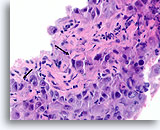

Ductaal carcinoom, Borst FNA, Celblok.

Er is duidelijk gerandomiseerde polariteit van een cytologisch atypische en vrijelijk stratificerende populatie ductale cellen aanwezig.

Ductaal carcinoom, Borst FNA, Celblok.

Er is duidelijk gerandomiseerde polariteit van een cytologisch atypische en vrijelijk stratificerende populatie ductale cellen aanwezig.